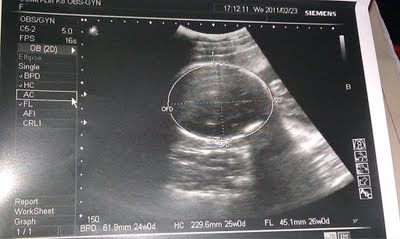

醫師是很好心的每次都會替Schumi照超音波看一下Schumi心臟,頭圍,四肢 還有體重等等

只是...我每次都看不太懂超音波的畫面..(可能我太沒有想像力了吧??) 但頭和心臟我看得出來

這次Schumi的體重約800g,醫師說剛剛好(上面這一張圖是Schumi的胎頭喔!)